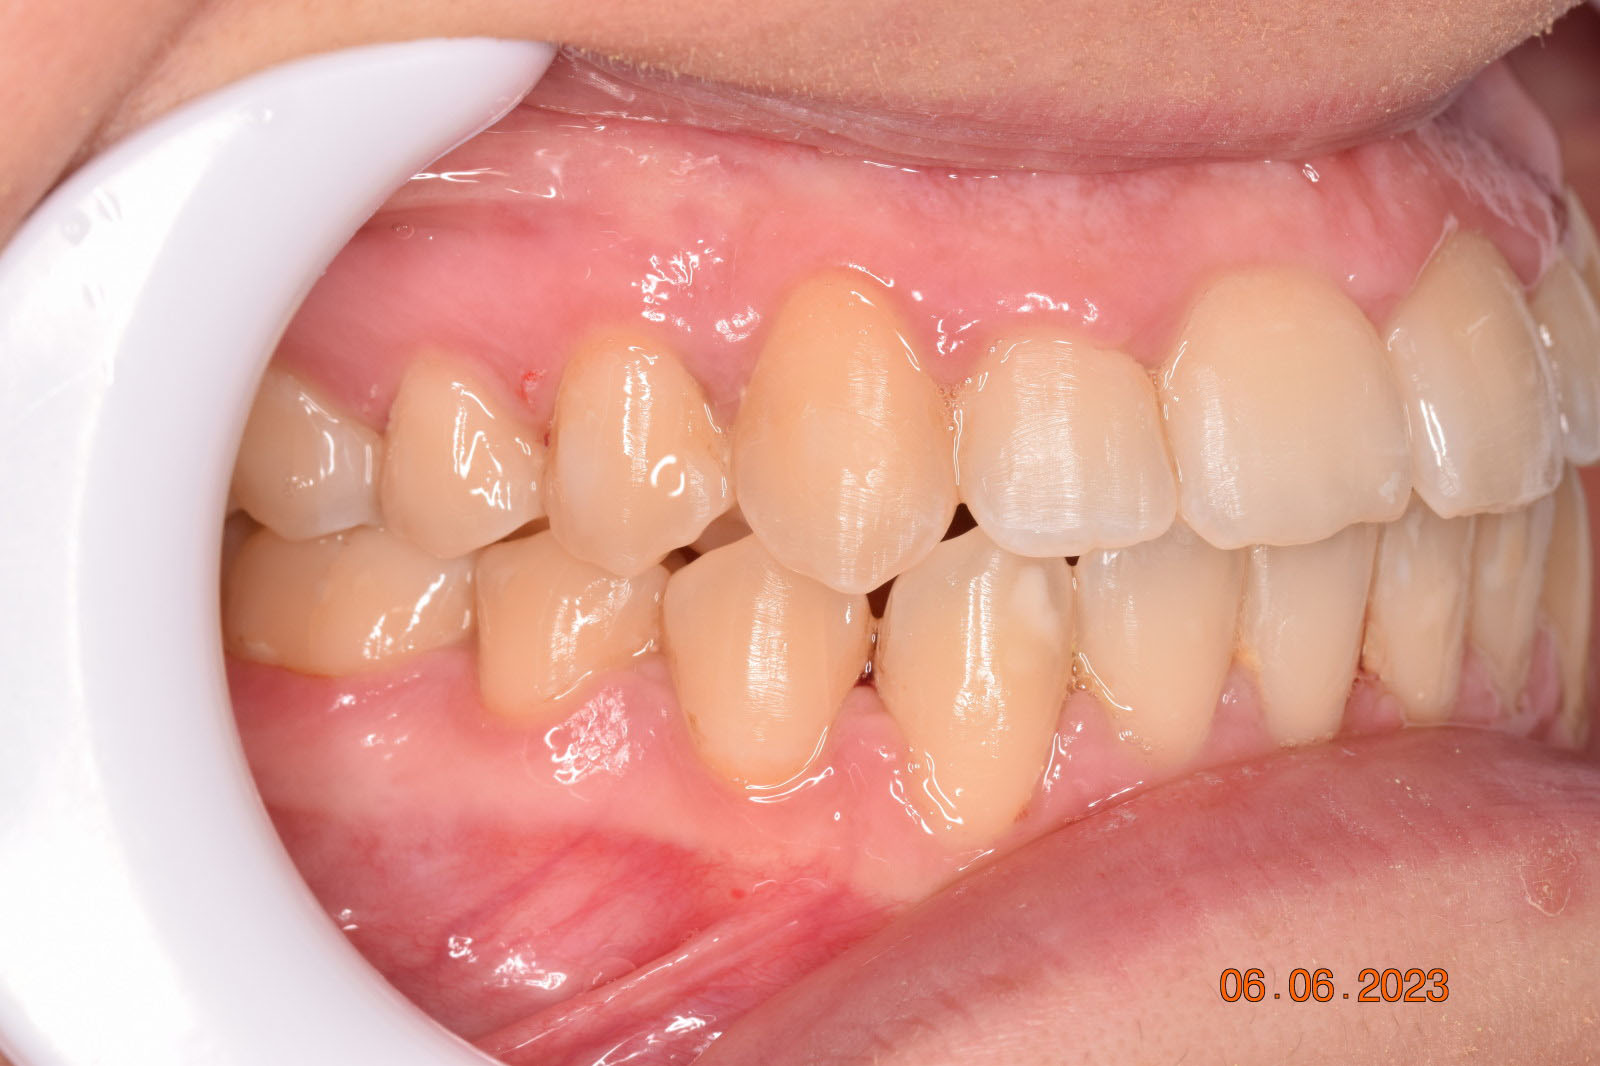

A 27-year-old female patient presented with class III malocclusion, 15 mm crowding in the upper arch, an anterior open bite, a lateral crossbite, and a total ABO score of 29. Her facial profile was straight with a retrusive maxilla, and the upper and lower incisors were retroclined. An extreme lack of midface support was also noted, and the constricted dental arches resulted in a poor smile width and dark buccal corridors. No myofunctional investigations were performed at the time, as they were initially considered unnecessary.

Adhering to the principles of Face First Orthodontics, the primary objective was to increase midface support by expanding the upper maxilla, fixing the cross bite, and aligning the teeth. Closing the open bite was a secondary objective.

The treatment began in 2017. Given the patient’s preference for less visible brackets, Damon Clear brackets were selected. High torque upper cuspids and low torque upper incisors were chosen to offer the best torque control for upper arch development. For the lower arch, there were no alternative bracket configurations available. Bite turbos were applied to the upper second molars.